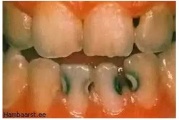

Lutipudelikaaries